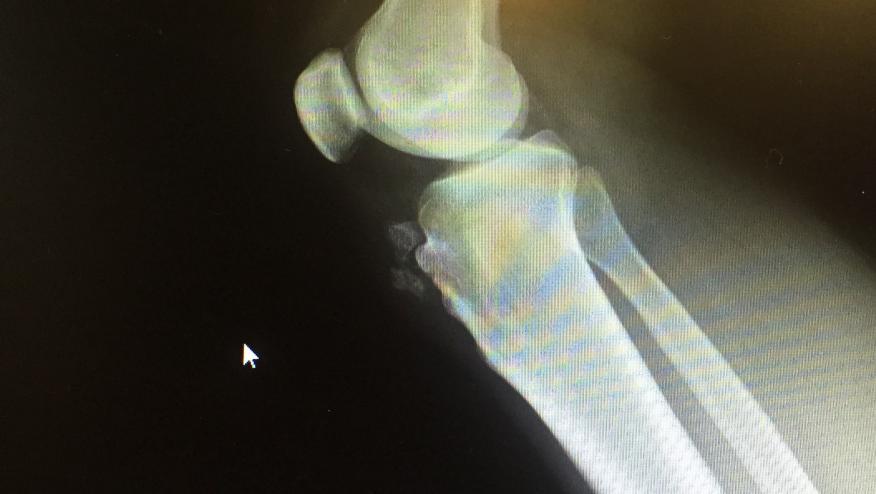

Right Knee Pain - What's Your Dx? Save

A 36 year-old white male butcher has right knee pain for 3 weeks. He noted a similar episode 5 years earlier and admits to a traumatic fall on that knee years ago. He denies fever, redness, warmth, other joints or other past medical problems. He only takes OTC ibuprofen prn.

Radiologist Diagnosis: Old Osgood-Schlatter with ossified fragments,accompanied by anterior soft tissue swelling. If chronic or persistent, MRI would be advised.

Case and Radiograph submitted by Daniel Ricciardi, MD (Brooklyn, NY)